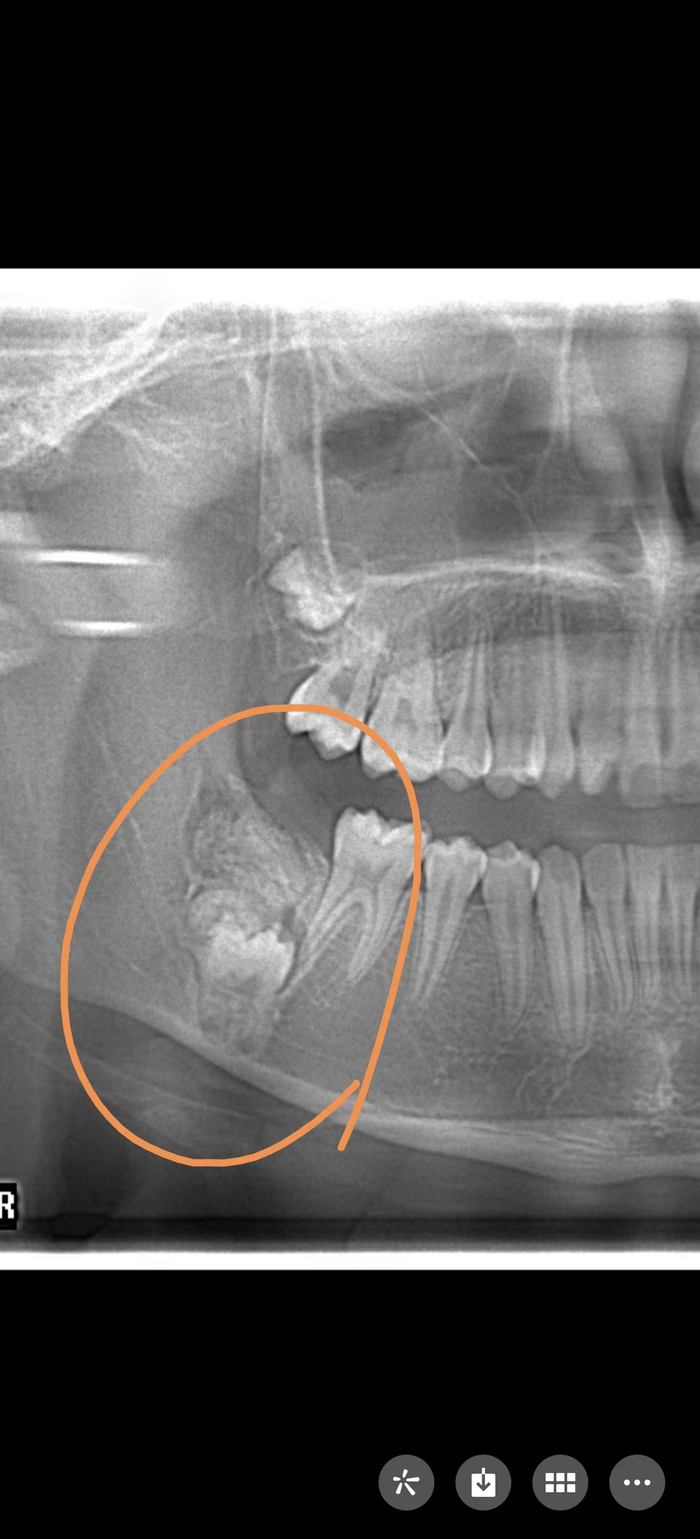

12岁的小雅(化名)因为牙齿不齐前来上海市儿童医院口腔科做正畸治疗,拍片发现,小雅的右下颌骨内发生了瘤样病变,因此导致其右下第2恒磨牙在顶出来的途中遇到“埋伏”,无法正常长出。

小雅的影像学报告。本文图均为上海市儿童医院 供图